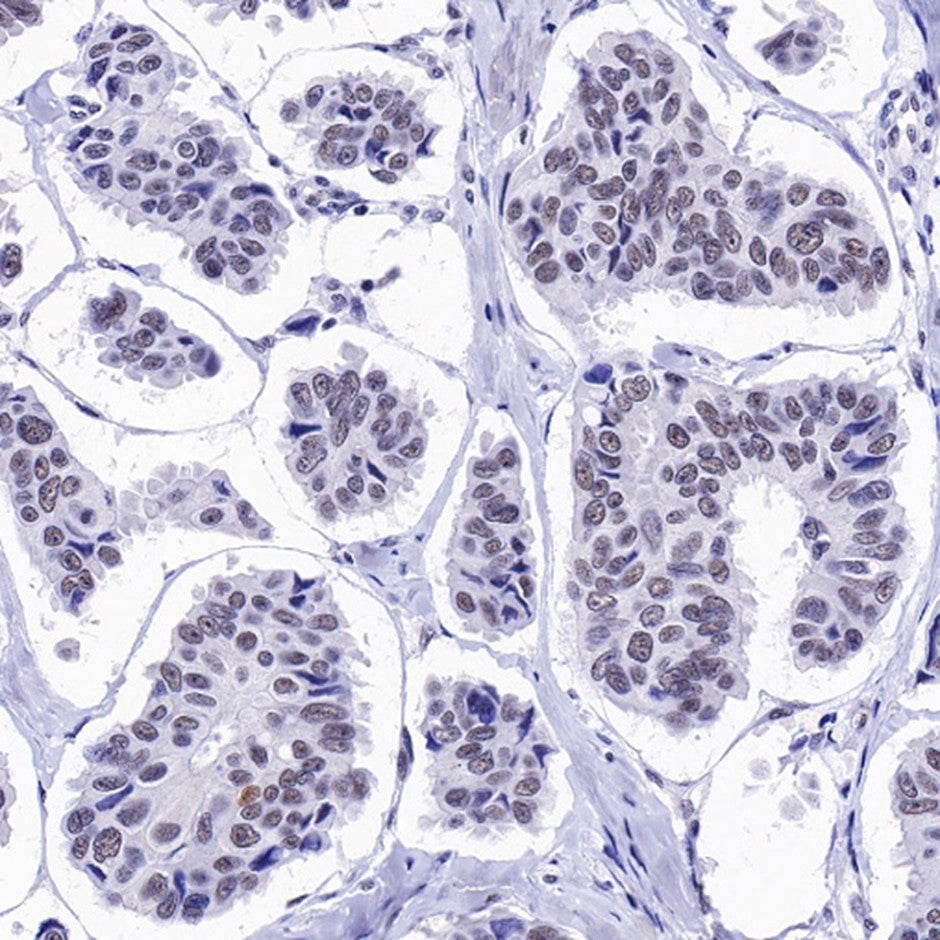

- Superior detection performance: Excels in WB (clear specific bands), IF/IHC (displays nuclear speckled/diffuse localization), and IP (supports interaction studies).